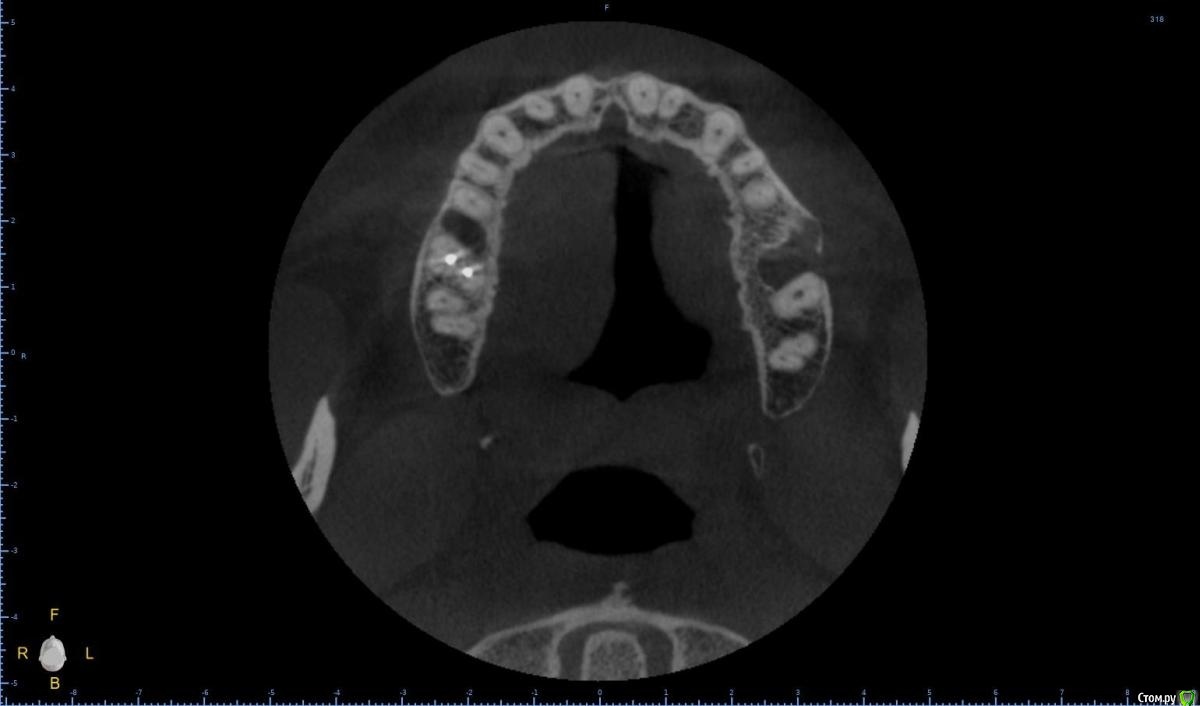

Raystom Опубликовано 20 февраля, 2021 Поделиться Опубликовано 20 февраля, 2021 Обратилась пациентка с неприятными ощущениями в области зубов 26, 27, во рту эти зубы показались мне темнее остальных, на КТ видна вот такая красота. Каков план лечения в таких ситуациях? Попробовать отделить пазуху от грануляций или просто удалить и после лечения ЛОРа идти на закрытие ОАС? Как после восстанавливать кость? И какие временные промежутки. Понимаю, что многие скажут при таких вопросах передать другим, но это не мой вариант. Мб есть литература по подобным случаям? Ссылка на комментарий

It'sGeorgy Опубликовано 20 февраля, 2021 Поделиться Опубликовано 20 февраля, 2021 А что именно смущает? Что дефект с пазухой сообщается? Так закроете после удаления, ничего страшного. ЛОРу, имхо, там делать нечего пока еще.Недавно был подобный случай: А вообще, судя по тем скринам, которые вы выложили, я бы пациента терапевтам показал для начала. Ссылка на комментарий

Raystom Опубликовано 20 февраля, 2021 Автор Поделиться Опубликовано 20 февраля, 2021 А что именно смущает? Что дефект с пазухой сообщается? Так закроете после удаления, ничего страшного. ЛОРу, имхо, там делать нечего пока еще.Недавно был подобный случай:12.png23.png22.png А вообще, судя по тем скринам, которые вы выложили, я бы пациента терапевтам показал для начала.Именно, что с пазухой. С терапевтами общались, при попытке препарирования зуб "мягкий", как кариозный судя по их словам Ссылка на комментарий